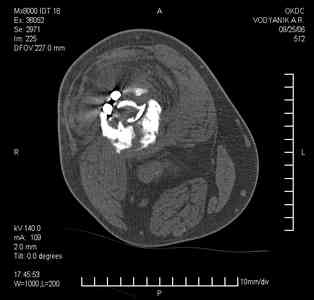

Уважаемые коллеги,В ортопедическое отделение обратился пациент: мужчина 47 лет, который в течение 4-х лет дваждыполучил травму костей, образующих правый коленный сустав. В 2002 v внутрисуставной оскольчатыйперелом проксимального метаэпифиза правой большеберцовой кости; в 2005 v внутрисуставнойоскольчатый перелом дистального метаэпифиза правой бедренной кости. В обоих случаях в разных лечебных учреждениях проводилось оперативное лечение переломов.При осмотре в отделении на основании результатов клинического осмотра и данных визуальныхметодов обследования поставлен диагноз:тугой ложный сустав дистальной трети правой бедренной кости, состояние после накостногоостеосинтеза перелома типа 33-В2.2 ; несросшийся перелом надколенника; неправильно сросшийсяперелом латерального мыщелка правой большеберцовой кости, состояние после металлоостеосинтезаперелома 41-В2.2; сочетанная осевая деформация правой ноги: варусная деформация правого бедра,вальгусная деформация правой голени; посттравматический артроз коленного сустава 4 ст по Kellgren-Lowrence; выраженное нарушение функции ходьбы и опоры. Внешний вид ноги больного, данные рентгенографического обследования и избирательно выделенные компьютерные томограммы приведены в приложении. В именах КТ использовано кодирование уровня по АО, т.е. _41, например, означает проксимальную треть голени.В отделении намечен v очень предварительно v следующий план лечения: 1. Иметь ввиду перспективу тотального эндопротезирования коленного сустава. 2. С учетом п.1 при проведении действий, направленных на устранение ложного сустава бедренной кости не использовать материалы, не подвергающиеся трансформации. 3. В ходе операции, направленной на устранение ложного сустава: А. удалить все металлоконструкции; Б. ревизовать зону пролежня под пластиной на бедре, при наличии признаков достаточной жизнеспособности кости выполнить остеопериостальную декортикацию, дрилинг ложа пластины; В. Удалить рубцовую ткань по плоскости ложного сустава, и в пространстве между костными форагментами, насечь обращенные друг к другу поверхности. Ввести штифт с блокированием (например Stryker с учетом особенностей расположения дистальных блокирующих винтов у этойконструкции). Осуществить остеосинтез с учтанением варусной деформации бедренной кости. Пространство в зоне ложного сустава и пустоты в метафизе бедренной кости заполнить резорбирующимся цементом на основе гидроксиапатита кальция. Для дистальной фиксации использовать винты с переменным шагом резьбы. Вариант:, винты вводить после заполнения метафиза цементом. Дополнительные виды создания межфрагментарной компрессии во встречно-боковом направлении обсуждаются. Г. Быть готовым к кровопотере. Д. Учесть высокий риск инфекции, тромбоэмболических осложнений. Е. Вопрос о внешней иммобилизации решить по результатам оценки стабильности остеосинтеза. Вариант - одноосевой стержневой аппарат для шунтирования гвоздя с модулем на голени и дистракцией коленного сустава в течение 3-5 недель. Просим вашей критики намеченного плана и конструктивных предложений. С уважением к сообществу, Ординатор В.С. Саплин

Движения приличные, есть за что бороться. Такая ротация голени кнаружи, если она действительно есть (для уточнения можно сделать КТ на уровне обоих метафизов и бедреных, и берцовых ксотей, не меняя положение ног во время съемки), большого значения не имеет. А уж на фоне всего остального тут - вообще говорить не о чем.